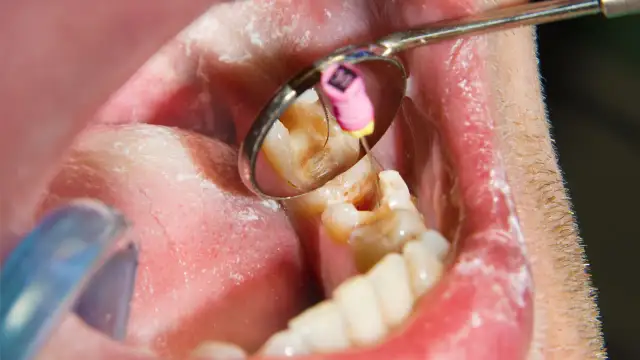

Ropa z zęba - co naprawdę usuwa i kiedy do dentysty?

Ropa z zęba - co realnie ją usuwa? Dowiedz się, kiedy domowe sposoby nie wystarczą i jakie objawy alarmowe wymagają pilnej wizyty u dentysty.